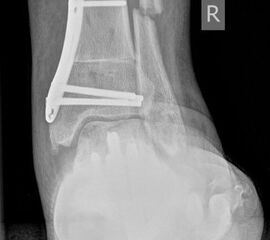

• posttraumatisch (Abb. 5)

• Fuß belastet dp und seitlich (Abb. 14 und 15)

• Saltzman view (Abb. 16)

Zum Lesen der Bildbeschreibung und zur Vollansicht bitte die Bilder anklicken. Bilder: A. Simon

Typische Merkmale der Standard-Seitaufnahme des Fußes im Stand

• Knöchelgabel ist außen rotiert

• Talus und Calcaneus verlaufen fast parallel

• Sinus tarsi ist einsehbar

• Subtalare Gelenklinie verläuft horizontal und ist breit einsehbar

• Der Abstand Malleolus medialis zum Os naviculare ist verkürzt

• Der Calcaneus erscheint verkürzt

• Der Krümmungsscheitel des Fußes ist erhöht

• Calcaneus pitch ist meist erhöht, der Rückfuß Equinus ist eher selten 12